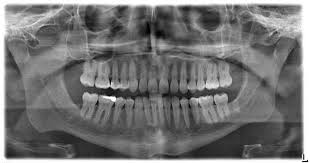

Panoramic Dental X Ray Showing A Crowding With A 10 Years Old Child Characterized By The Overlapping Of The Inciso Wisdom Teeth Wisdom Tooth Extraction Dental